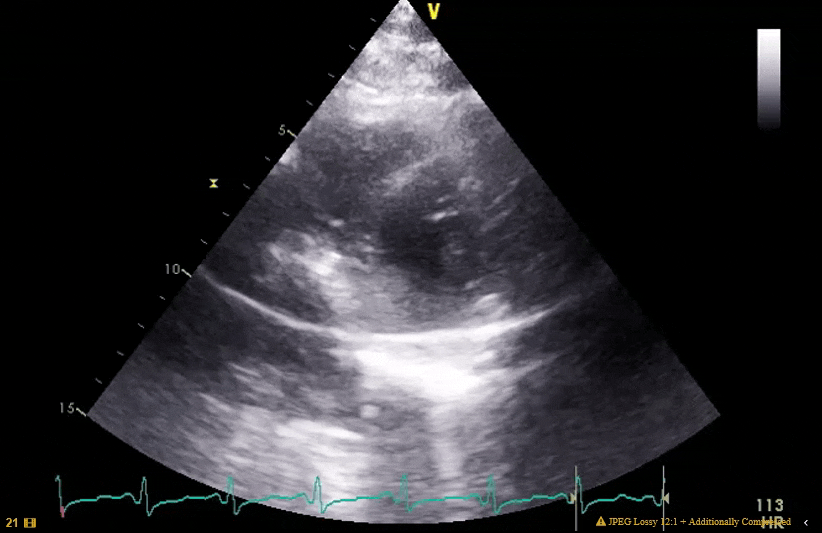

Embolized IAS occluder device?

Wow, strong work! It’s an amplatzer septal occlusion device that embolized after attempted deployment. Unable to retrieve in cath lab, came emergently to OR for open retrieval.

looks like an AV canal defect vs atrial septal rupture on the 4C ME view with an RVAD or other cannula in the RV. Other posters pointed out possible embolized valve or misdeployed PV, which would also make sense. There is a tricuspid valve in the correct position.

No AV canal defect. Just a foreshortened ME4, approaching a ME5. Was focused on getting a good X-plane of the embolized device, not necessarily getting the correct “view”. Good eye on the atrial septum. Patient had a large PFO and atrial septal aneurysm. I can see how you might think atrial septal rupture from that clip alone though.

Yes, it embolized after attempted deployment, but there is no catheter in the image I posted. In the ME4/5, the linear echo density closer to the tricuspid valve is the device, the more apical echo density is just a moderator band.